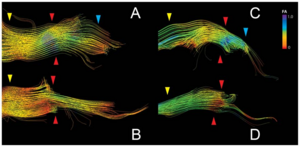

Publication: PLoS One. 2015 Oct 7;10(10):e0139434. PMID: 26444010 | PDF Authors: Tax CM, Chamberland M, van Stralen M, Viergever MA, Whittingstall K, Fortin D, Descoteaux M, Leemans A. Institution: Image Sciences Institute, University Medical Center Utrecht, Utrecht, The Netherlands. Background/Purpose: Fiber tractography plays an important role in exploring the architectural organization of fiber trajectories, both in fundamental neuroscience and in clinical applications. With the advent of diffusion MRI (dMRI) approaches that can also model "crossing fibers", the complexity of the fiber network as reconstructed with tractography has increased tremendously. Many pathways interdigitate and overlap, which hampers an unequivocal 3D visualization of the network and impedes an efficient study of its organization. We propose a novel fiber tractography visualization approach that interactively and selectively adapts the transparency rendering of fiber trajectories as a function of their orientation to enhance the visibility of the spatial context. More specifically, pathways that are oriented (locally or globally) along a user-specified opacity axis can be made more transparent or opaque. This substantially improves the 3D visualization of the fiber network and the exploration of tissue configurations that would otherwise be largely covered by other pathways. We present examples of fiber bundle extraction and neurosurgical planning cases where the added benefit of our new visualization scheme is demonstrated over conventional fiber visualization approaches. Funding:

|